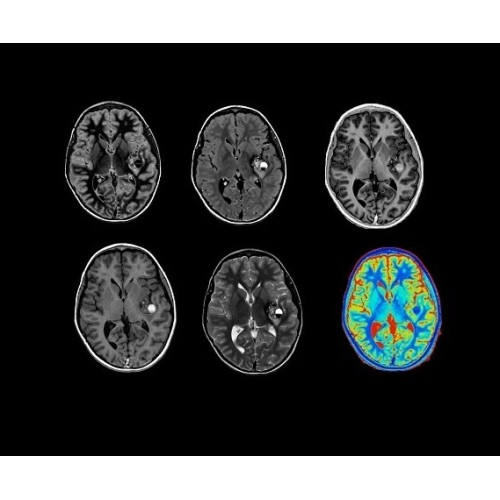

SIGNA PET/MR 3.0T — это гибридная система, в которой совмещаются две принципиально разные технологии — магнитно-резонансную томографию (МРТ) и позитронно-эмиссионную томографию (ПЭТ). Система отличающийся высокой чувствительностью и эффективностью и предназначена для диагностики в области онкологии, неврологии, кардио-васкулярных исследований, исследований воспалительных процессов.

Компания GE Healthcare представляет революционную, полностью интегрированную систему SIGNA PET/MR1, в которой сочетаются времяпролетная технология (TOF) и возможности напряженности магнитного поля 3.0 Тл. Мы поможем вам поднять исследования на более высокий уровень. SIGNA PET/MR позволяет достичь впечатляющей точности и скорости исследований, а благодаря новейшей технологии реконструкции Q.Clear2 качество изображений улучшается в два раза. Кроме того, в систему включен полный набор клинических приложений и гибких катушек для проведения любых видов исследования, открывая для вас возможности визуализации, о которых вы даже не догадывались.

Кроме того, в результате использования технологии TOF и инновационной технологии реконструкции Q.Clear вы сможете добиться прекрасного соотношения сигнал/шум. А благодаря технологии нулевого времени эхо (ZTE) визуализировать костную структуру без ионизирующего излучения. Все эти разработки для улучшения качества сканирования и точности анализа помогут вам использовать весь потенциал ПЭТ/МРТ.

Система SIGNA PET/MR предлагает впечатляющие клинические возможности и открывает доступ к наиболее полным пакетам программных приложений.

• Q.Clear — в основу технологии легли накопленные знания о том, как минимизировать помехи при реконструкции и получить четкое изображение. При значительном улучшении качества изображения сохраняется точность расчетов. Сочетание технологии TOF и реконструкции Q.Clear — ваш надежный помощник для получения точных и достоверных данных.

Стандартный пакет приложений SIGNA Works позволит вам достичь желаемых результатов в клинической практике благодаря набору высокоэффективных средств визуализации. Программные приложения, входящие в состав данных клинических пакетов, включают широкий спектр контрастов, функции обработки 2D- и 3D-данных, а также возможность коррекции артефактов движения. SIGNA Works предоставляет набор инструментов, необходимых для проведения эффективного клинического исследования.

• Специальный пакет приложений для измерения и сравнения объемных изображений ЦНС с нормами поможет вам в диагностике нейродегенеративных заболеваний, а дополнительные инструменты визуализации — в постановке точного диагноза с помощью бета-амилоидов и радиоизотопных маркеров ФДГ.